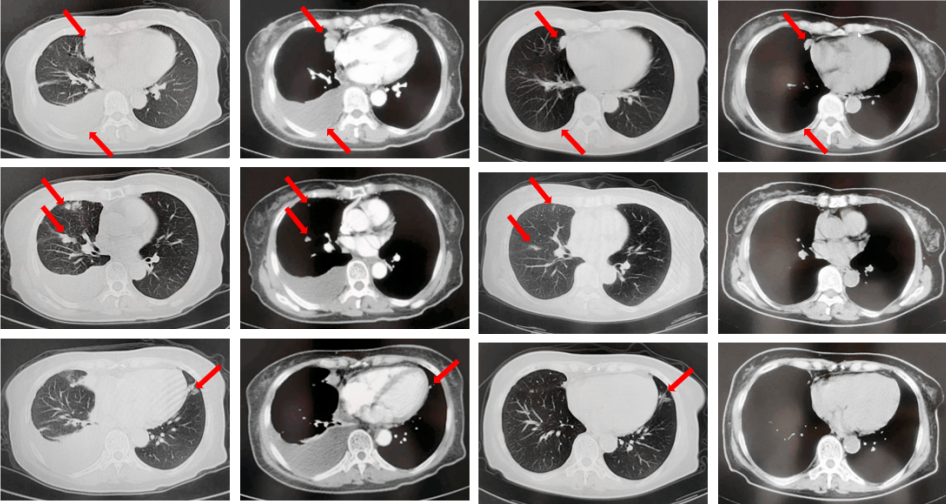

2022年7月至2022年11月行贝伐珠单抗联合培美曲塞/顺铂方案治疗6周期,2周期后评效PR,4周期后评效SD-(如图1)。第6周期治疗结束后患者自行终止治疗。

图1:由左至右分别展示基线(A.)及一线治疗后改变(B.和C.)。红色箭头指示病灶位置,由上至下分别为右肺肿物、右侧胸膜转移病灶及胸腔积液、左侧胸膜转移病灶、多发纵隔淋巴结肿大。

2023年3月患者因咳嗽伴胸闷复查出现全面PD。2023年3月-2023年4月重启原方案贝伐珠单抗联合培美曲塞/顺铂治疗2周期。2023年5月复查评效PD。行左锁骨上淋巴结穿刺,病理回报:左锁骨上见异型细胞,考虑为癌可能性大。组织NGS基因检测:MET基因扩增(变异倍数)2.0倍,TP53错义突变,PD-L1(22C3):TPS 75%。2023年5月-2023年8月改行替雷利珠单抗联合紫杉醇脂质体治疗4周期,2周期后评效SD。(如图2)

图2:A.代表一线治疗停药后病情进展,右肺上叶肿物、右侧胸膜转移灶及纵隔淋巴结较前增大、增多,右侧胸腔积液较前增多;B.原方案重启后复查评效右肺上叶肿物及纵隔淋巴结较前略饱满,右侧胸腔积液较前明显增多;C.更改二线治疗方案后整体病灶较前无显著变化。